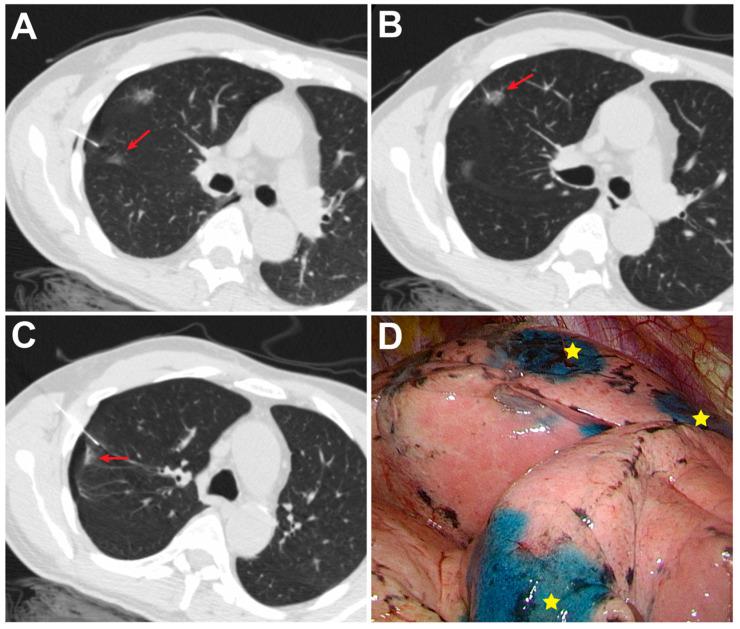

同时注射专利蓝染料有助于术前 CT 引导下多个肺结节的定位。

Simultaneous Patent Blue Dye Injections Aid in the Preoperative CT-Guided Localization of Multiple Pulmonary Nodules.

: Clinically, a major challenge of multiple nodule localization is puncture-related pneumothorax, which may hamper the successful localization. This study aims to investigate and compare the efficacy and safety of the simultaneous and sequential patent blue dye (PBD) injections for identifying multiple pulmonary nodules during preoperative CT-guided localization. : Sixty-one consecutive patients with multiple pulmonary nodules who underwent preoperative CT-guided localization with PBD injections between January 2020 and December 2020 were retrospectively enrolled. Of these patients, 31 patients with 64 nodules who underwent simultaneous injections were designated as the simultaneous group; the remaining 30 patients with 63 nodules who underwent sequential punctures were designated as the sequential group. The clinical and radiological features, technical information, pathological results, and procedure-related variables and complications of the two groups were reviewed and analyzed. : The localization success rate of the simultaneous group was higher than that of the sequential group (100% [64/64] vs. 93.7% [59/63], = 0.041). The incidences of pneumothorax (32.3 vs. 33.3%, = 0.929) and pulmonary hemorrhage (6.3 vs. 3.0%, = 1) were not significantly different between the two groups, and all cases were minor, which did not require further intervention. Additionally, a significantly lower radiation dose (2.7 vs. 3.5 mSv, = 0.001) and a shorter procedure time (20.95 vs. 25.28 min, = 0.001) were observed in the simultaneous group than in the sequential group. : Compared with the sequential method, simultaneous PBD injections may improve the localization success rate with a shorter procedure time and less radiation exposure if the patient with multiple pulmonary nodules can be approached in a single position. Further prospective studies are needed to validate these results.

摘要

临床上,多发结节定位的一个主要挑战是与穿刺相关的气胸,这可能会妨碍定位的成功。本研究旨在探讨和比较同时和顺序注射专利蓝染料(PBD)识别术前 CT 引导下定位的多个肺结节的疗效和安全性。

回顾性纳入 2020 年 1 月至 2020 年 12 月期间因 PBD 注射行术前 CT 引导下定位的 61 例连续多发肺结节患者。其中 31 例 64 个结节行同时注射,设为同时组;其余 30 例 63 个结节行序贯穿刺,设为序贯组。比较两组的临床和影像学特征、技术信息、病理结果及与操作相关的变量和并发症。

同时组的定位成功率高于序贯组(100%[64/64]比 93.7%[59/63], = 0.041)。两组气胸发生率(32.3%比 33.3%, = 0.929)和肺出血发生率(6.3%比 3.0%, = 1)无显著差异,且均为轻微,无需进一步干预。同时组的辐射剂量(2.7 比 3.5 mSv, = 0.001)和操作时间(20.95 比 25.28 min, = 0.001)均显著短于序贯组。

与序贯法相比,如果能在一个体位接近多个肺结节的患者,同时注射 PBD 可能会提高定位成功率,同时操作时间更短,辐射暴露更少。需要进一步的前瞻性研究来验证这些结果。